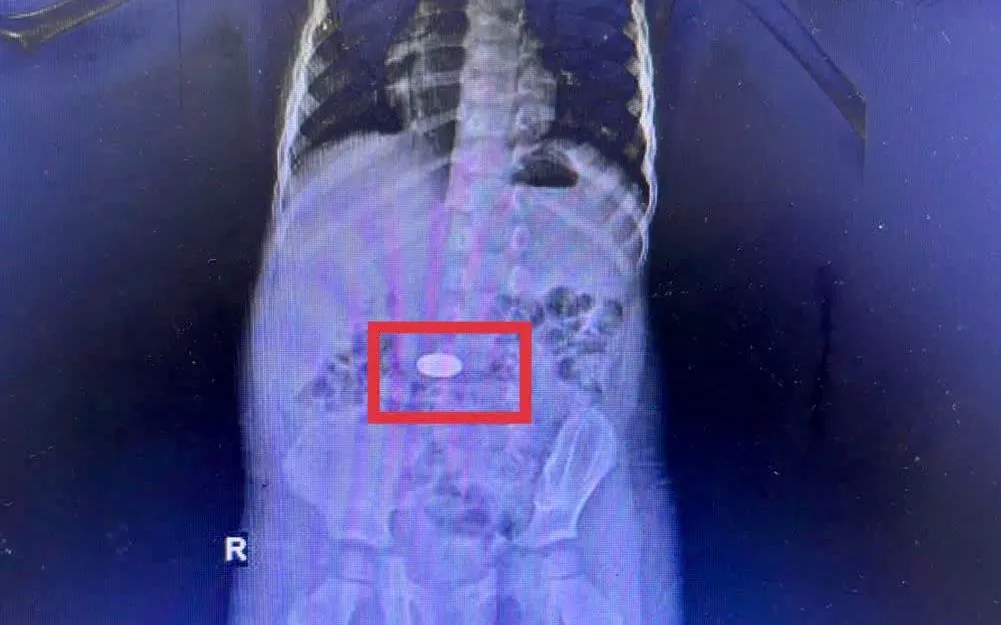

Tại Bệnh viện Đa khoa Khánh Hòa, các bác sĩ ghi nhận 5 trẻ nhỏ nhập viện vì hóc đồng xu trong thời gian ngắn. Một trường hợp điển hình là bé 3 tuổi, được đưa đến viện trong tình trạng quấy khóc, khó chịu. Kết quả chụp CT cho thấy dị vật nằm trong dạ dày. Các bác sĩ đã nội soi cấp cứu và lấy thành công đồng xu trong đêm, trẻ ổn định và xuất viện sau đó.